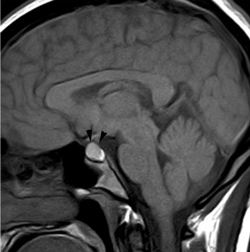

Figura 1A y B. TAC con contraste yodado, corte coronal, muestra un microadenoma lateralizado a izquierda (punta de flecha). Control a los 2 años. TAC con contraste yodado, corte coronal, demuestra aumento de volumen del microadenoma, lo que es infrecuente de observar en clínica (punta de flecha).

En los microadenomas el crecimiento tumoral es observado en una minoría de los casos (Figuras 1A y 1B), en contraste con los macroadenomas, los cuales cuando son encontrados en forma accidental (incidentalomas pituitarios) han demostrado un aumento de tamaño que varía entre 25 a 50%27-31.